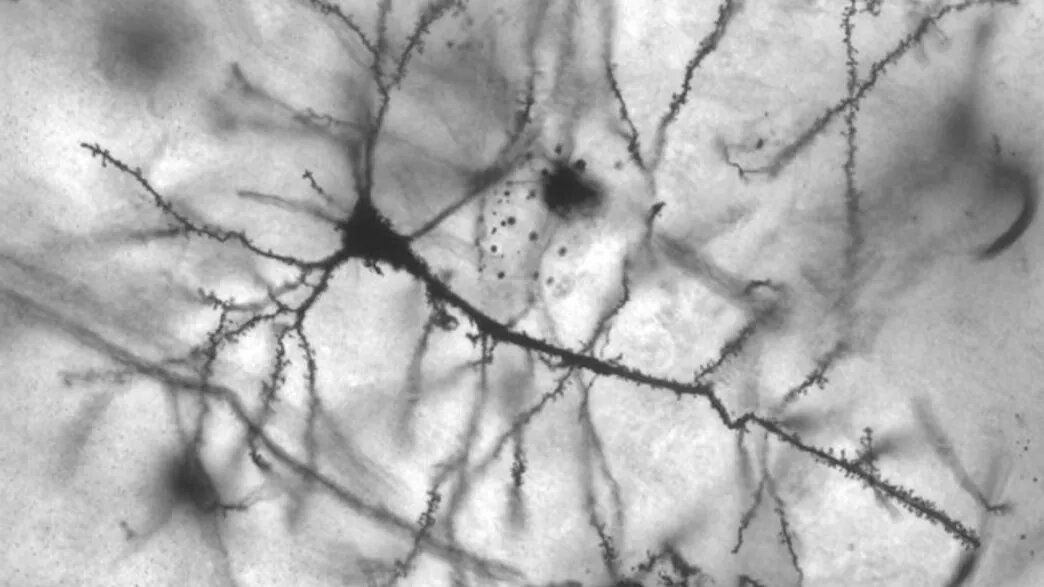

Гиппокампальный нейрон. Источник: Wikimedia Commons.

Следующим шагом ученых стало создание генетически измененных мышей со сверхэкспрессией белка Klotho. Такие мыши не только прожили дольше, чем мыши контрольной группы, но они также показывали лучшие результаты в тестах на память и обучаемость на протяжении всей жизни. Кроме того, повышение уровня Klotho привело к изменениям в двух областях мозга, критически важных для познания — гиппокампе и коре.

Клетки головного мозга связываются друг с другом с помощью молекул, называемых нейротрансмиттерами через небольшой промежуток между нейронами, который называется синапс. Одним из таких передатчиков является глутамат, который связывается с синаптическими рецепторами, такими как рецептор NMDA. Обучение и память укрепляет синаптические связи и включает согласованную деятельность этих рецепторов и глутамата. С возрастом эти функции ослабевают.

Ученые обнаружили, что у модифицированных мышей больше специфических субъединиц рецептора NMDA, называющихся GluN2B, в синапсах гиппокампа и коры в сравнении с контрольными мышами. Это субъединицы, как известно, играют основную роль в процессах обучения и памяти. Кроме того, когда исследователи использовали препарат, препятствующий работе GluN2B, они устранили влияние Klotho на процесс запоминания и обучения.